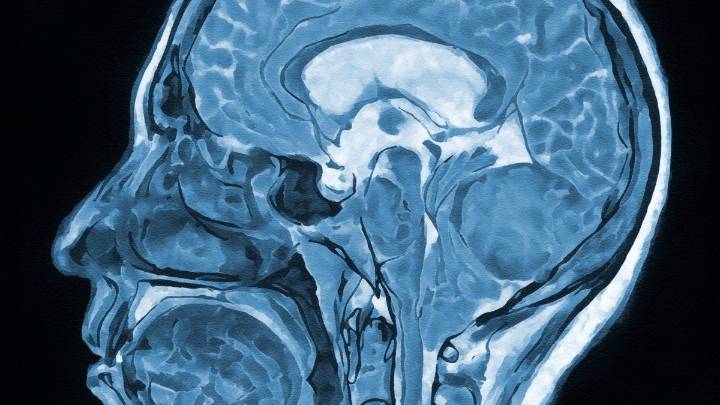

What are currently seen as three separate mental health conditions – depression , anxiety and post-traumatic stress disorder (PTSD) – could really be different aspects of the same underlying brain disorder.

In fact, the 14 most common mental health and neurodiversity conditions seem to really be just five clusters of closely related conditions. New Feature